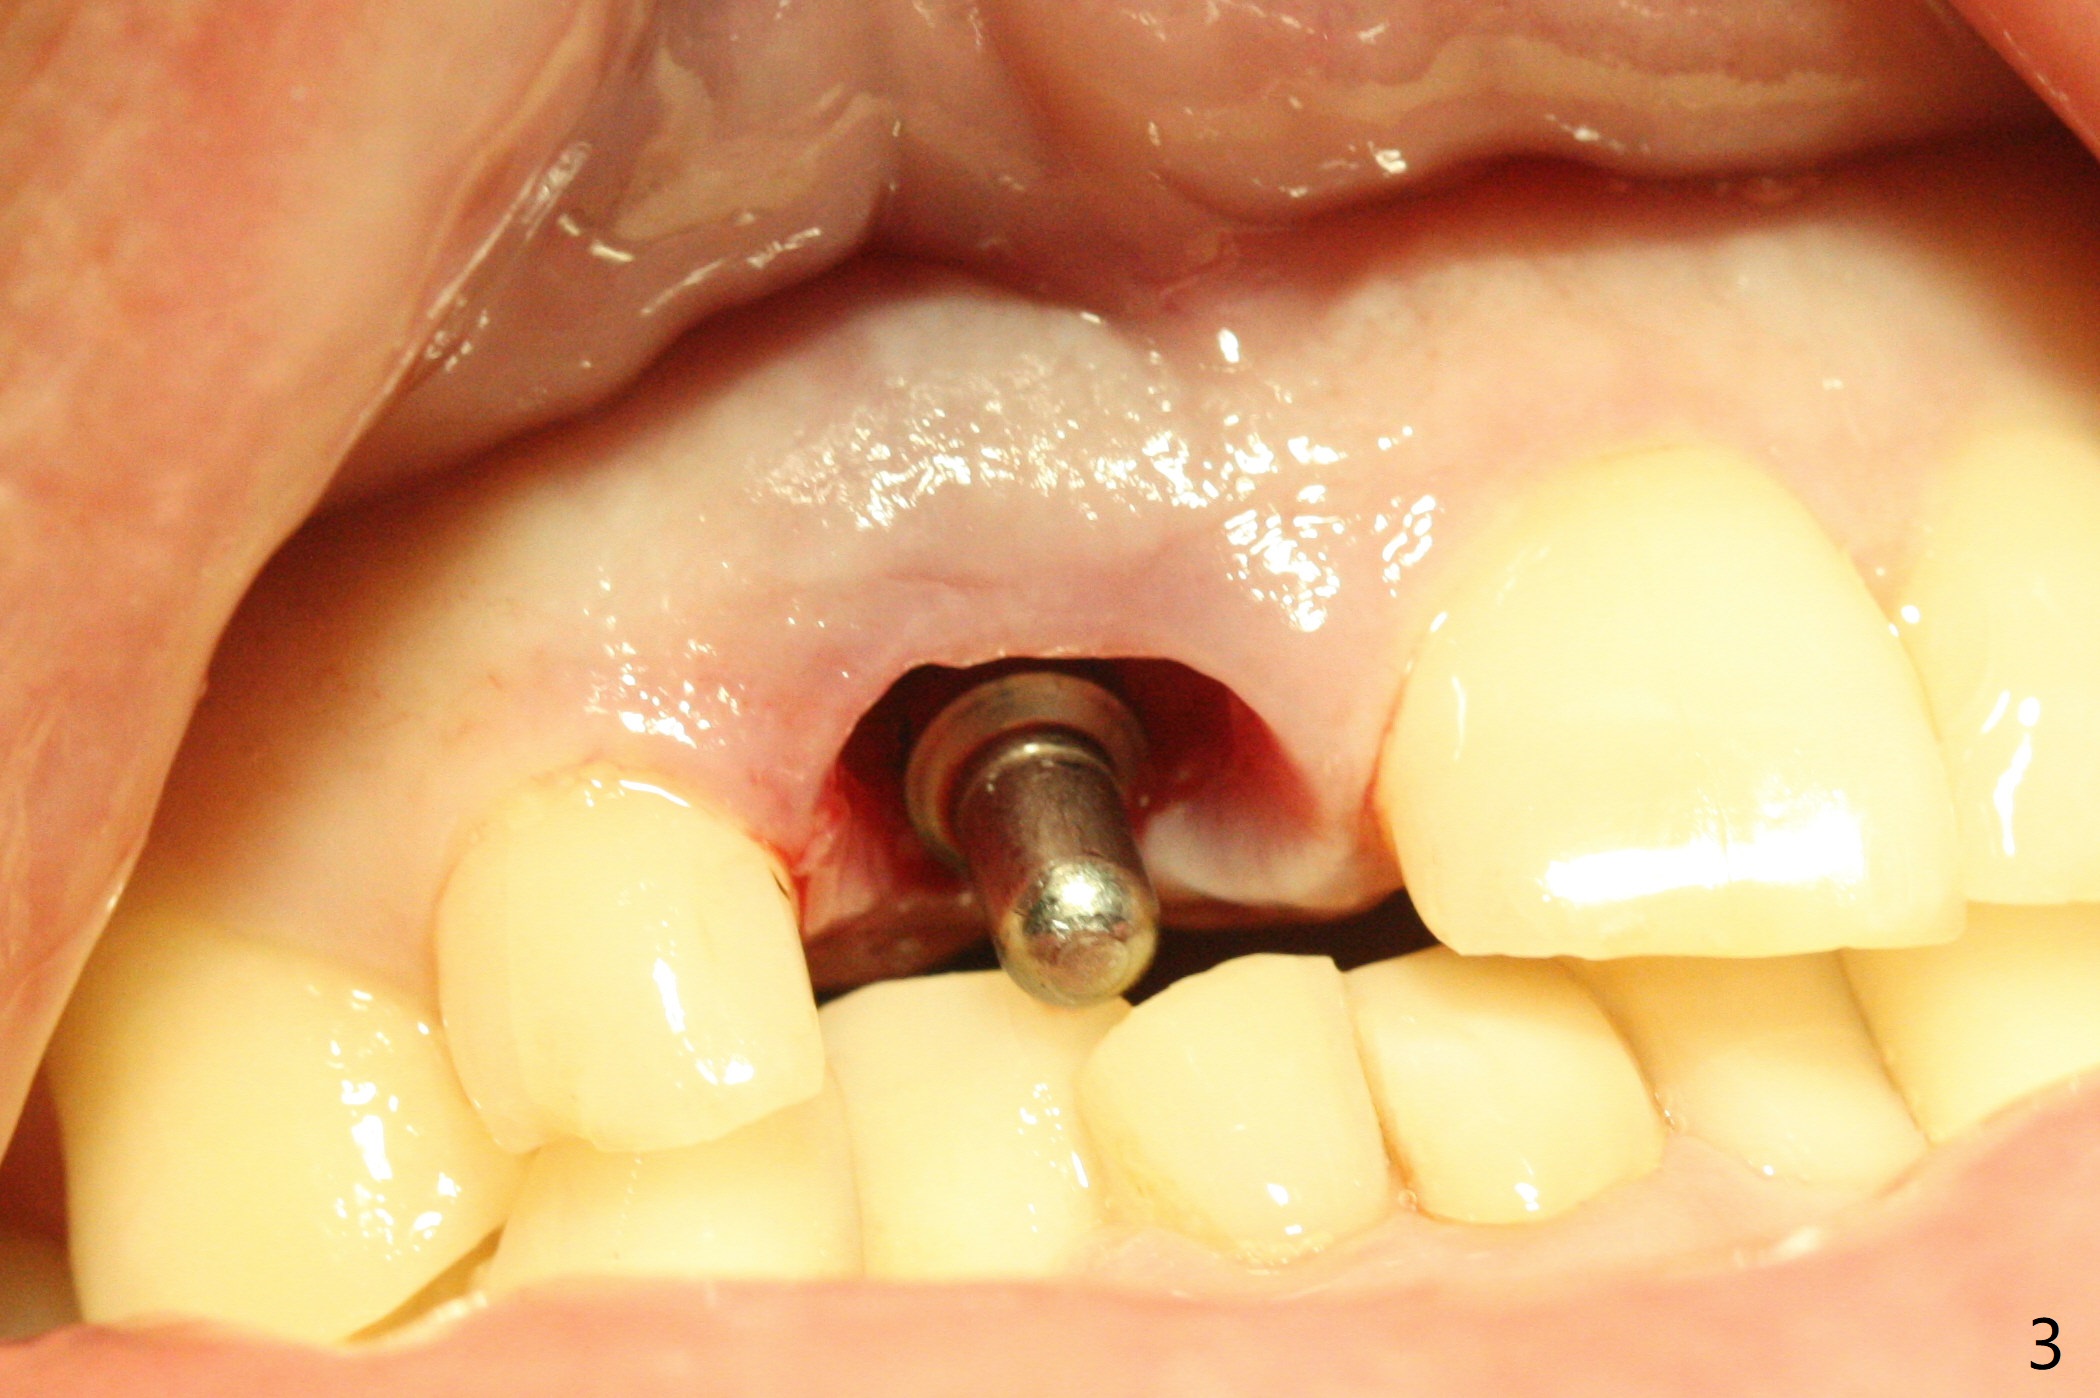

The buccal gingiva at #8 is erythematous (Fig.1: *), which is associated with the tooth fracture line (Fig.2 with granulation tissue: *). The buccal plate remains intact. Osteotomy is initiated in the palatal wall of the socket (Fig.3,4). The initial osteotomy depth is 16 mm (Fig.5); the trajectory is going to be adjusted as shown by arrows. The trajectory improves when a 3.8x15 mm dummy implant is placed (Fig.6). The definitive implant (3.8x16 mm) appears to be placed at an appropriate level (Fig.7). A 4.5x3 mm temporary abutment is inserted for an immediate provisional. As routine, Vera Graft is placed in the buccal gap. The buccal gingival erythema reduces without tenderness 1 week postop (Fig.8). Although the provisional is unstable, there is no bone loss 2 months 20 days postop (Fig.9). Because of the loose provisional (partial detachment from the underlying temporary abutment), impression is taken earlier (3 months postop, Fig.10,11). Due to the pointed abutment tip, the crown is redone 3 times. By the time of cementation (nearly 5 months postop), the socket appears to have healed (Fig.12).